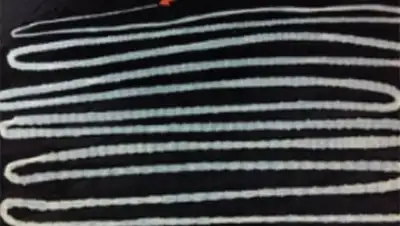

Медики обследовали его, но первичный осмотр не выявил никаких патологий. Во взятых у мужчины анализах обнаружили яйца бычьего цепня. После проведения медикаментозной терапии пациент избавился от паразита: длина червя достигала 6,2 метра.

Как пояснили медики, пациент подхватил паразита из-за любви к сырой говядине. Длина бычьих цепней, живущих в кишечнике человека, может достигать 10 метров. Их жизнь внутри человеческого организма вызывает тениаринхоз, который характеризуется приступообразными болями в животе, тошнотой, слабостью, изменением аппетита, головными болями, головокружением, а также запорами или поносами.

Фото: The New England Journal Medicine